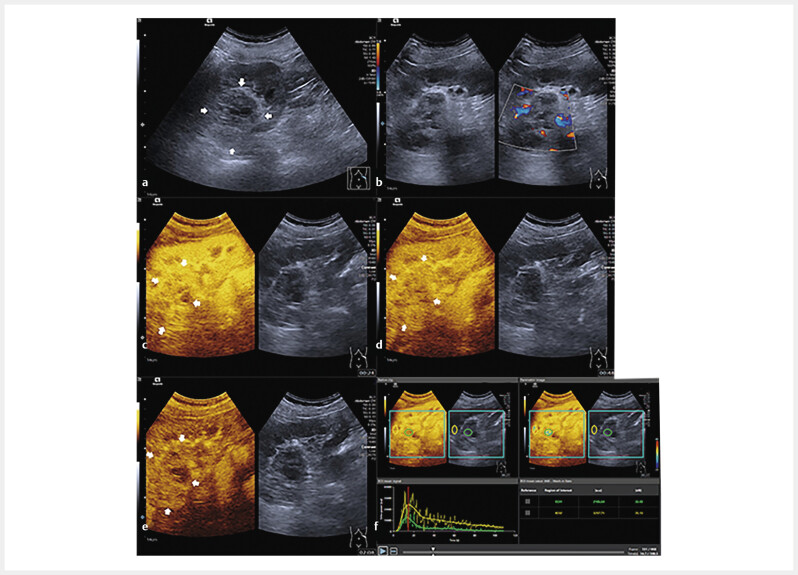

Materials and methods: Patients with surgery resection and histopathologically proven RCC lesions were included. B-mode ultrasound (BMUS) and contrast-enhanced ultrasound (CEUS) were performed one week before surgery. SonoVue was injected as the contrast agent. VueBox (Bracco, Italy) was used for the quantitative analysis. According to the histopathological and immunohistochemical results, patients were classified into two groups: active angiogenesis and inactive angiogenesis. Time intensity curves (TICs) and quantitative parameters were compared between two groups.

Results: From July 2023 to November 2023, a total of 50 patients (13 females and 37 males, mean age 61.1±11.1 years) were included. The mean size of the lesions was 39.4±2.7 mm. Patients were classified into the active angiogenesis group (n=30) and the inactive angiogenesis group (n=20). On BMUS, 68.0% (34/50) of RCCs were visualized as hypoechoic lesions with ill-defined borders and irregular shapes (P>0.05). During cortical phase of CEUS, 72.6% (23/30) of RCCs with active angiogenesis were visualized with hyperenhancement (P=0.027). Only 30.0% (9/30) of RCCs with active angiogenesis showed hypo-enhancement in the parenchymal phase (P>0.05). Compared to the inactive angiogenesis group, TICs of the active angiogenesis group revealed faster and greater enhancement in the cortical phase, slower decline during the parenchymal phase, and an increased area under the curve. Among quantitative parameters, the active angiogenesis group showed the higher ratio of wash-in rate and wash-in perfusion index (P<0.05).

Abstract Image